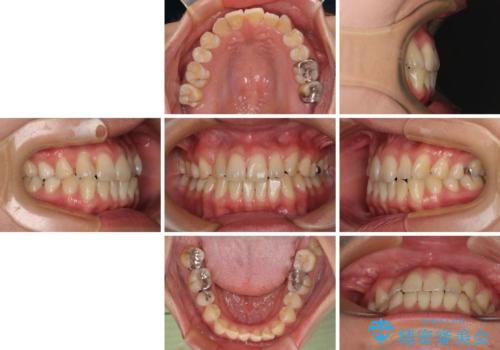

上下前歯のデコボコを気にして来院された患者様です。

ワイヤー矯正でもマウスピース矯正でも可能でしたが、短期間で、自身の手を煩わせることなく治療を行いたいとのことで、ワイヤー装置にて矯正治療を行うこととしました。